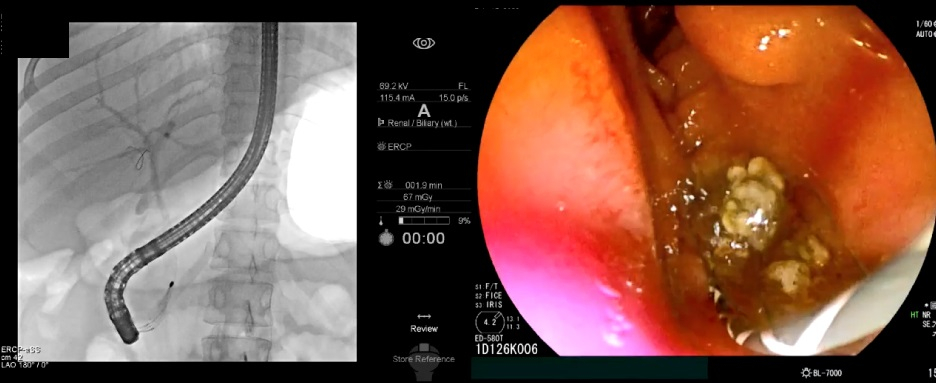

초음파내시경으로 담관결석이 관찰되면 내시경적 역행성 담췌관조영술(이하 ERCP)을 통해 담관결석을 제거한다. ERCP는 특수내시경과 방사선을 이용한 시술로, 내시경을 십이지장까지 삽입하고 십이지장 유두부를 통해 담관에 관을 넣고 조영제를 주입해 담석의 정확한 위치를 확인한다. 이후 미리 넣어놓은 가이드선을 따라 바스켓 또는 풍선 기구를 담관으로 넣어 담석을 뺀다. ERCP로 담관결석을 제거한 뒤에도 재발을 막기 위해 담낭담석을 없애는 담낭절제술이 필요하다.

ERCP는 개복 등 수술적 치료 없이 내시경시술을 통해 담관결석을 제거할 수 있지만 시술 난도가 높고 침습적 치료이기 때문에 드물게 부작용과 합병증이 발생할 수 있다. 특히 십이지장 유두부가 매우 좁아 결석을 빼내기 위해 유두부 괄약근을 절개하는 과정에서 출혈·천공 등의 위험이 있다. 가장 흔한 시술 관련 합병증은 췌장염이며, 대부분은 경증이나 심각한 경우 중증도의 췌장염이 나타날 수 있다. 그런데도 ERCP는 수술 없이 시술만으로 담관결석을 제거할 수 있고 비교적 신속한 치료가 가능하다는 장점이 더 크다.